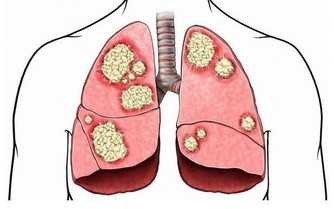

右臉頰長痘可能是肺的問題

右臉頰痘痘是肺部有炎症的反映。如果你肺火上升、喉嚨乾燥、痰多咳嗽,留意一下右臉頰痘痘。

建議:禁食易敏食物。停止吃海鮮和芒果、酒類食物等易敏食物,過敏會讓你的氣管、支氣管、肺部更加不適。